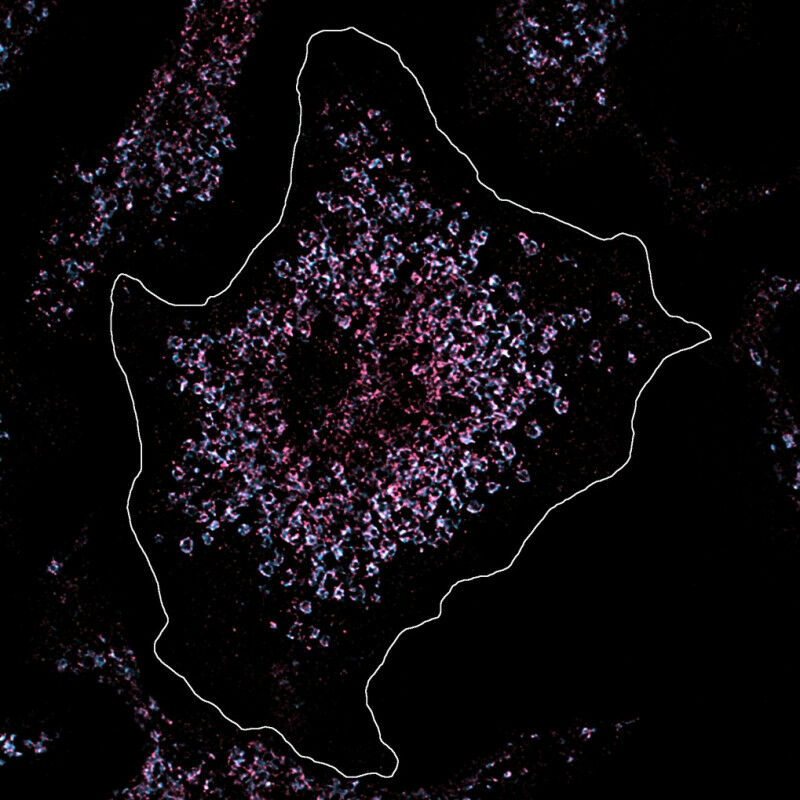

In this cell, Toll-like receptor 7 was stained pink in order to analyse its amount and position under the microscope. The cell is healthy and the amount of Toll-like receptor is normal. The situation is different in the immune cells of lupus patients, which have a significantly increased number of receptors, whereby the body's own genetic material is recognised and the chronic inflammation of lupus is triggered. © MPI f. Infection Biology/ Fenja Blank

Researchers were able to trace a form of the autoimmune disease lupus back to a single mutation. In this cell, Toll-like receptor 7 was stained pink in order to analyse its amount and position under the microscope. The cell is healthy and the amount of Toll-like receptor is normal. The situation is different in the immune cells of lupus patients, which have a significantly increased number of receptors, whereby the body's own genetic material is recognised and the chronic inflammation of lupus is triggered. MPI f. Infection Biology/ Fenja Blank - Sometimes a single mutation in our genetic make-up is enough to cause disease. This is also the case with the autoimmune disease lupus. Lupus causes severe inflammation throughout the body and can have a serious impact on the lives of those affected.